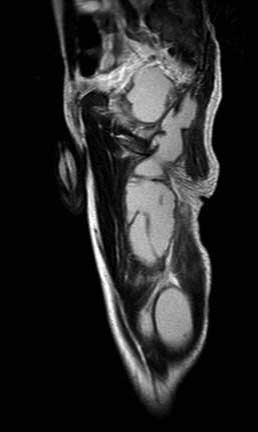

Просмотрел все предоставленные исследовании и первый МРТ снимок показывает, что ни псоас и не прямая кишка не вовлечены в процесс. Медиальнее от псоас слева имеется абцесс идущий сверху. На втором боковом изображении белое пятно это сердце, потому что находится выше диафрагмы. Спереди передная стенка, а пятно сзади это начало абцесса.Третий и четвертые снимки показывают уровень таза и медиально расположенный многокамеральный абцесс идущий между мышцами.

Обычный снимок позвонка давно бы снял все сомнения, а дополнительные снимки показали бы откуда идет "холодный абцесс" . А сейчась смело можно заключить: ТВС из нижних отделов торокального позвонка.